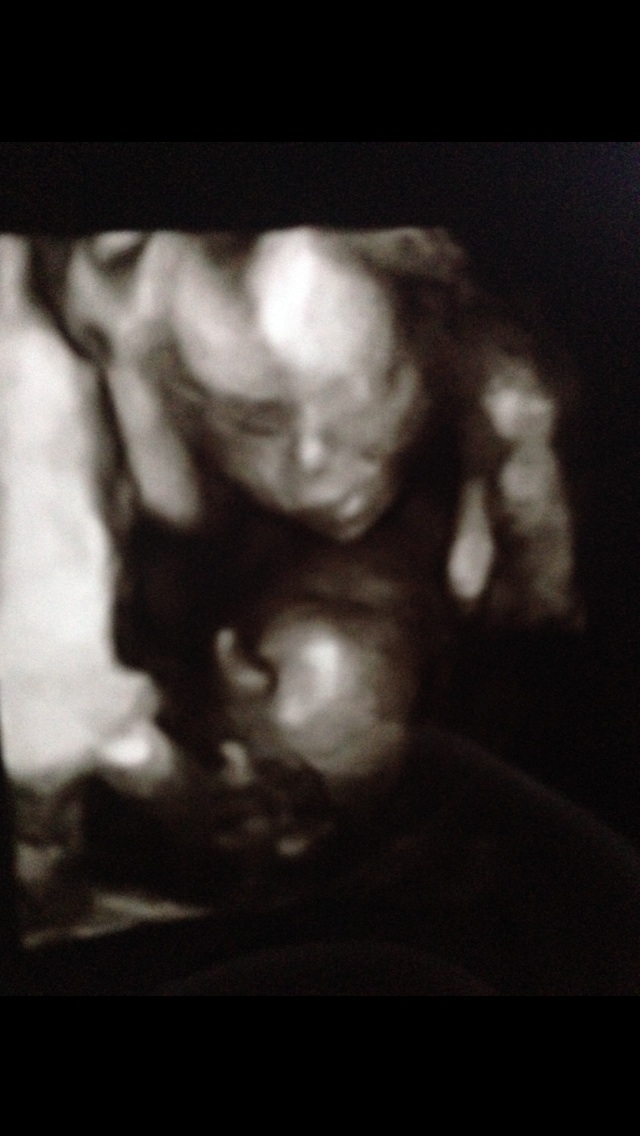

Any chance my 3rd boy could come out a girl?? 3dpic

I've been reading a lot of your posts about GD and I basically could of wrote them myself! Having my 3rd boy and suffering badly with gd it just won't go away. I keep saying to myself, if I pray ever night until the baby comes maybe the penis will go back inside and form a clitorus by the time baby is born! Can you all give an opinion of whether you think I have any chance they got the gender wrong in my scan this scan was taken at 16w 0d Attachment 17162